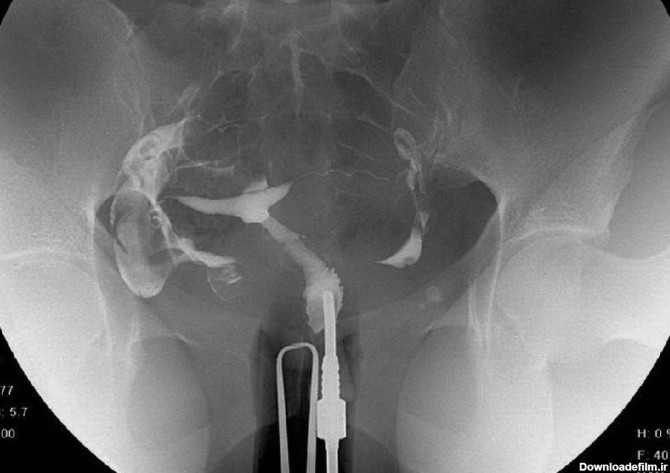

عکس رنگی رحم در کلینیک رادیولوژی مرکز درمان ناباروری ابنسینا، هم با بیحسی هم و هم با بیهوشی انجام میشود.تمام پرسنل این کلینیک خانم، و همگی بسیار مجرباند و نتیجه عکس بلافاصله پس از انجام آن توسط متخصص محترم رادیولوژی به مراجعان محترم داده میشود.شماره تماس برای دریافت نوبت: ۰۲۱-۲۳۵۱۹